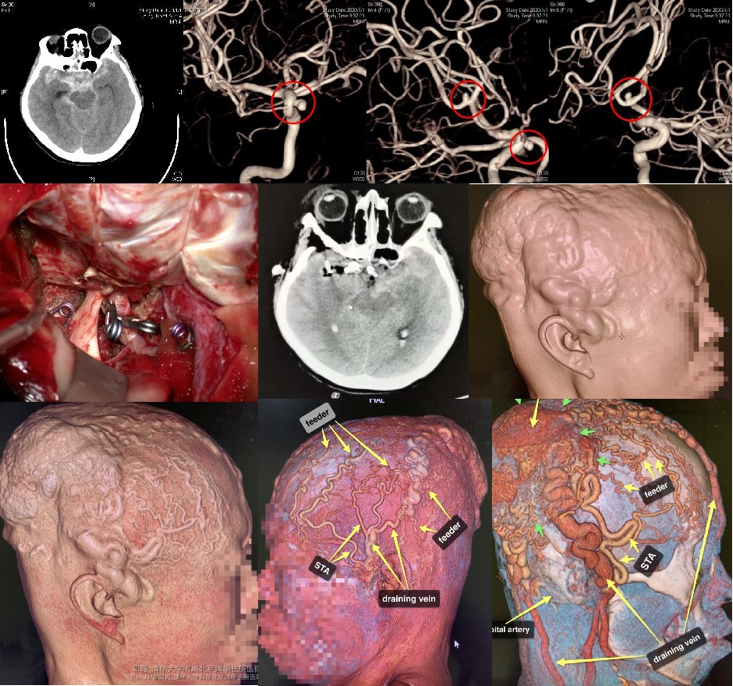

脑动脉瘤及颈动脉狭窄等血管性疾病是神经系统常见病和多发病,临床治疗中经常遇到一些比较复杂、疑难的病例,要制定合理的手术方案,影像评估至关重要。CTA、DSA可以帮助我们完成详细的血管形态检查评估,CT灌注成像可以判定脑组织灌注及代偿等情况,MRI可辅助甄别颈动脉斑块是否稳定,利用荧光造影可以术中评估手术效果,这些都是精准神经外科不可或缺的技术。

图9 CTA三维重建精准评估颅内及颅外复杂血管性疾病